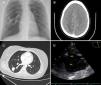

A 28-year-old woman, who had been subjected to a dental procedure two weeks before, consulted for seizures and fever. At oral cavity examination, palatine telangiectasias were evidenced, with no signs of dental infection. The chest X-ray showed a well-defined pulmonary opacity in the inferior right lobe (Fig. 1A) and a cerebral contrast CT scan evidenced a ring-enhancement lesion in the right parietal lobe suggesting a cerebral abscess (Fig. 1B). A thoracic CT scan was performed showing a 7mm pulmonary arterio-venous malformation (AVM) in the right inferior lobe (Fig. 1C). A contrast transesophageal echocardiogram confirmed a grade 3 right-to-left shunt (Fig. 1D, RA: right atrium; LA: left atrium; SVC: superior vena cava; IAS: interatrial septum). The cerebral abscess was drained and antibiotic treatment was completed (positive hemocultures for streptococcus sp). Endovascular embolotherapy of the pulmonary AVM was performed. The final diagnosis was Rendu-Osler-Weber disease.